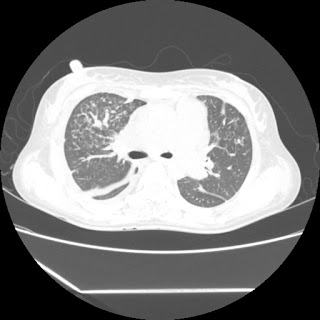

(HRCT)CT-Scan investigation done on 19Aug15 :

Series1